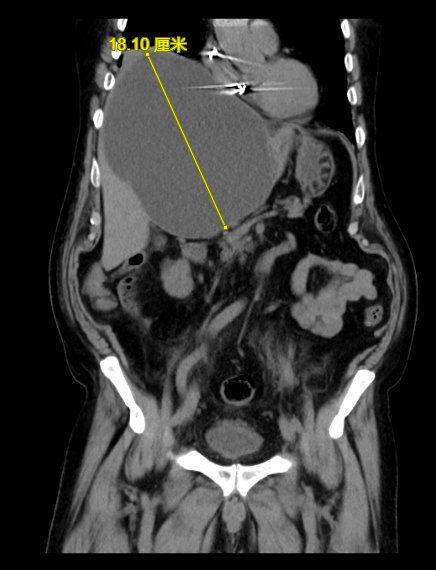

最近,一名81岁的男性患者因为“右上腹疼痛不适1周”就诊,入院查体发现皮肤、巩膜黄染,经过进一步检查,考虑腹痛原因为胆囊炎和肝巨大囊肿(图1,肝囊肿最大径18cm),巨大肝囊肿压迫肝脏内胆管,还导致了梗阻性黄疸,即皮肤、巩膜黄染。经过充分的术前评估,我们为该患者做了腹腔镜下胆囊切除和肝囊肿开窗术,术后患者的症状完全缓解,复查肝囊肿消失(图2)。体检发现肝囊肿,对于许多人来说可能是一个令人担忧的消息。然而,肝囊肿其实是一种常见的肝脏良性病变,大多数情况下并不需要过度担心,像上述患者的情况是比较少见的。本文将详细解释肝囊肿的相关知识,包括其分类、病因、症状、诊断、治疗以及预防等方面,帮助大家更好地理解和应对这一疾病。

图1